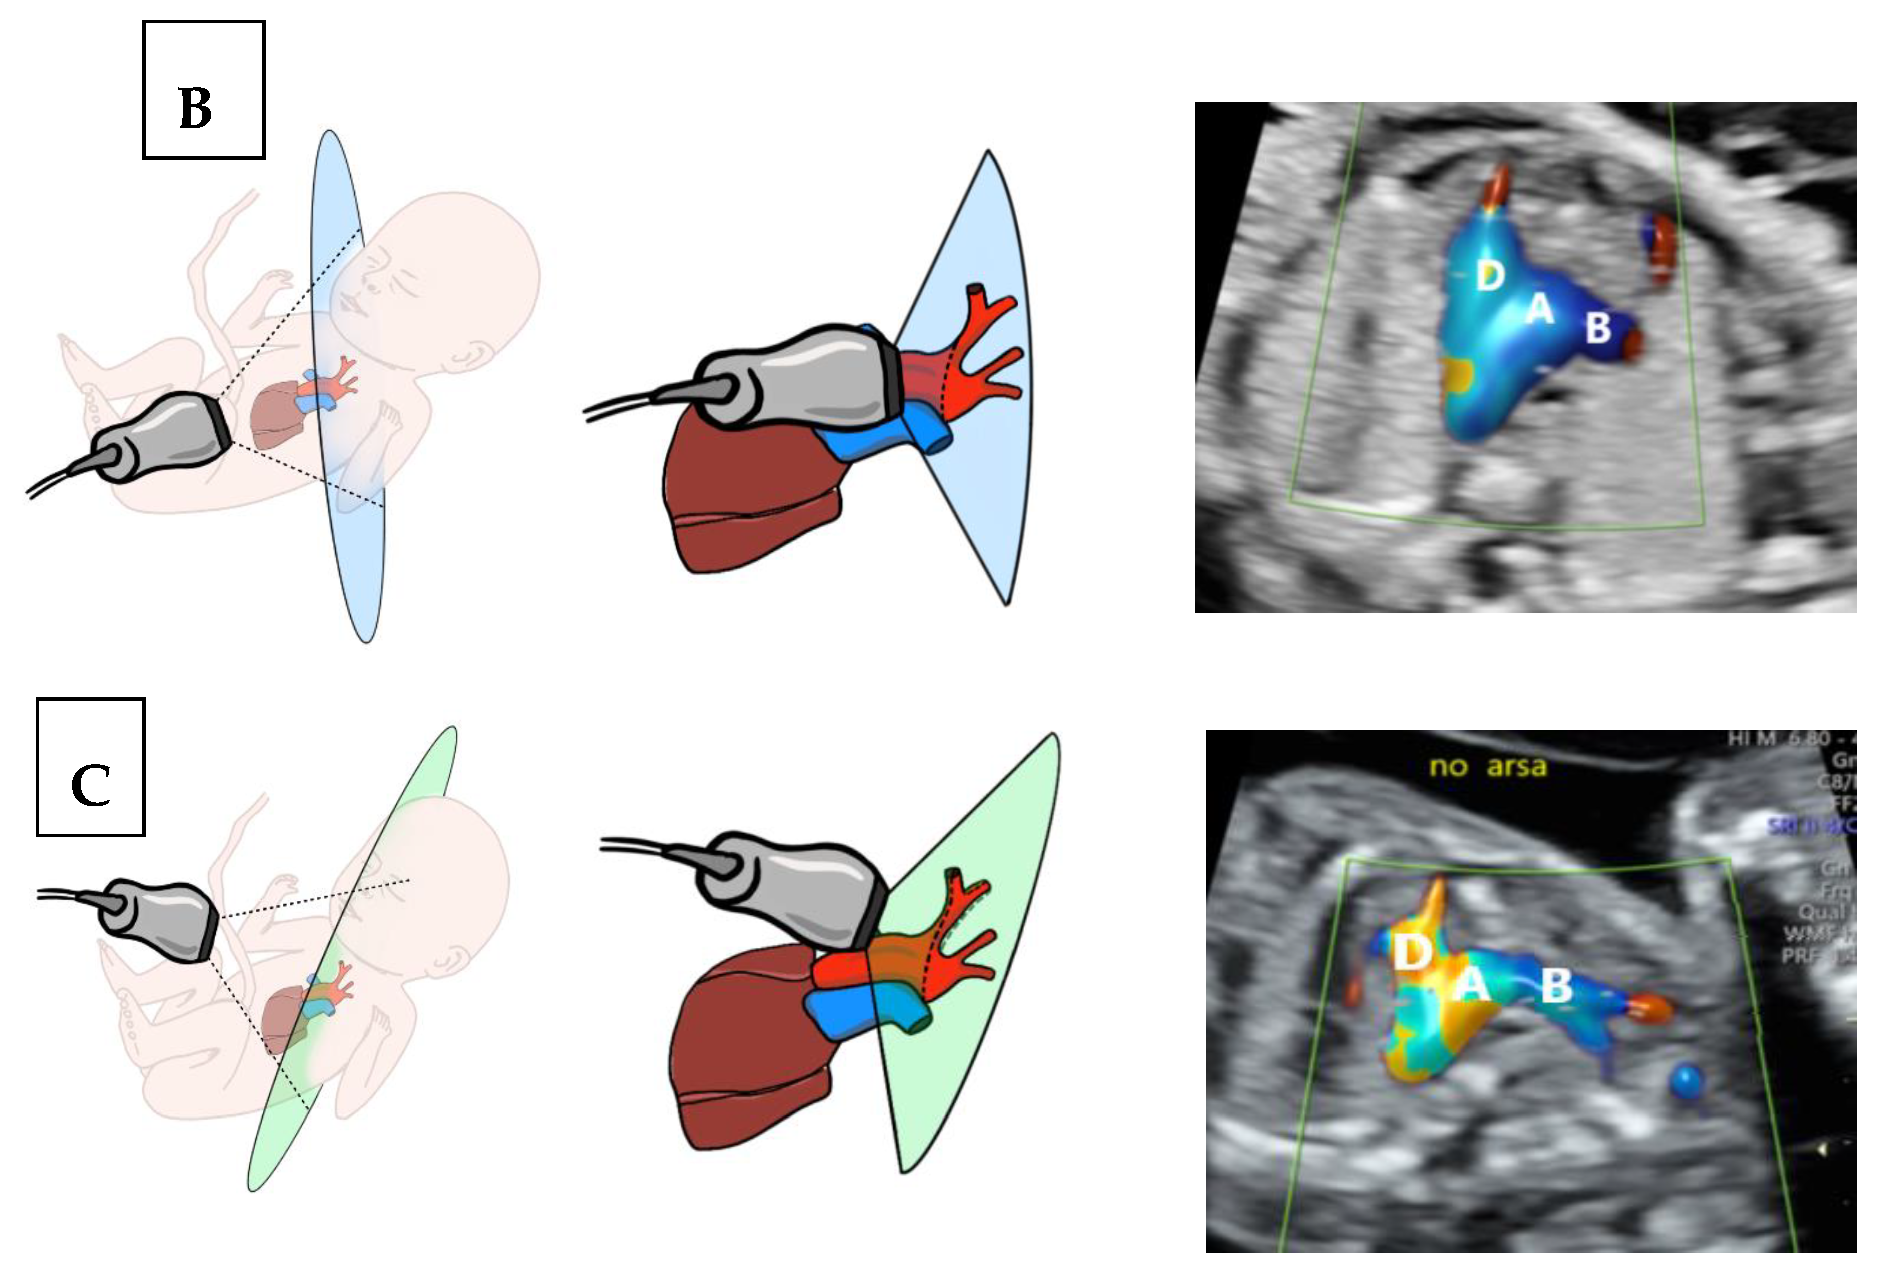

2.1. Description of the “No ARSA” Method